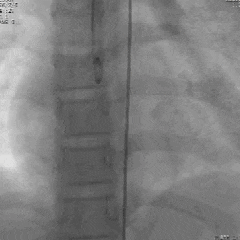

术后造影

升主动脉造影可见瘘管封堵完全,右心房无显影